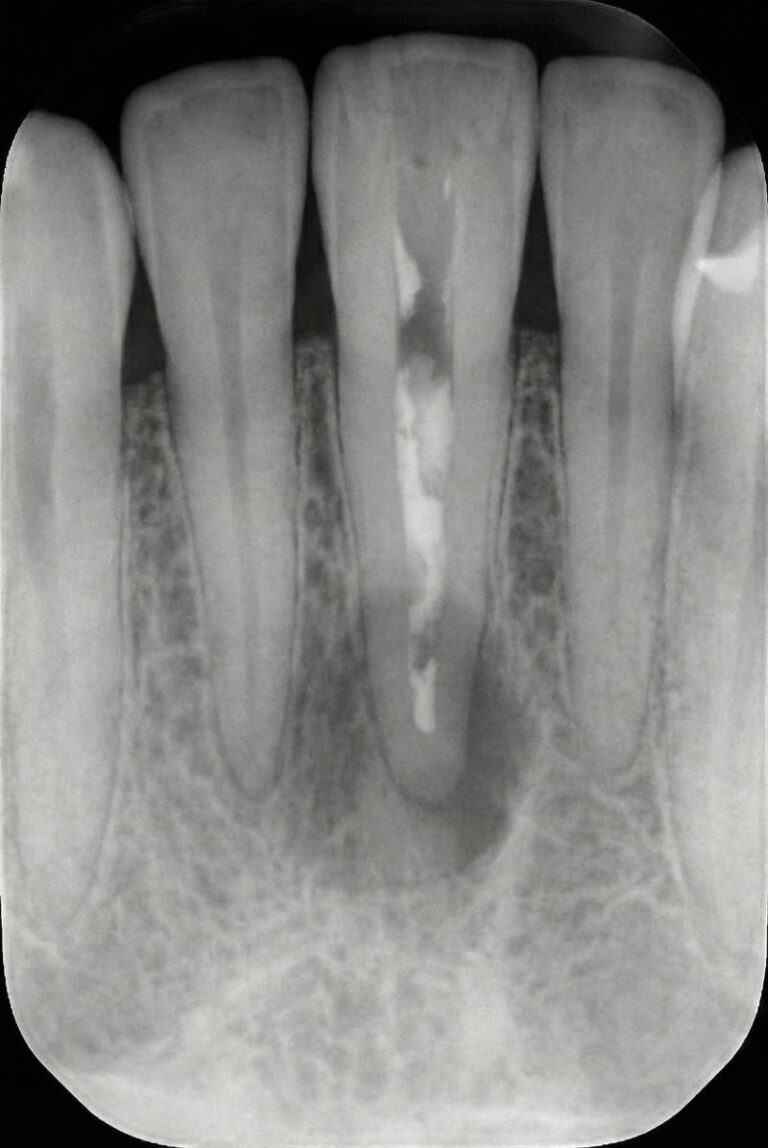

Retreatment of a root canal involves reopening the tooth, removing old gutta-percha and debris, disinfecting the canals and resealing them to eliminate persistent infection. This conservative procedure addresses hidden canals, complex root anatomy or new decay that compromised the original treatment. When standard retreatment is not enough, we may recommend an apicoectomy, which surgically removes the root tip and infected tissue through the gum.

When a first root canal doesn’t heal properly, lingering bacteria can cause pain, swelling and bone loss. Retreatment removes old filling material, cleans previously untreated or reinfected canals and reseals the tooth, helping preserve your natural root and avoid extraction or implants.

You may need retreatment if pain, swelling or sensitivity returns after a root canal. X-rays showing persistent infection or bone changes also indicate the need for evaluation.

Root canals may fail due to missed canals, complex anatomy, delayed crown placement, new decay or cracks that allow bacteria to re-enter the tooth.